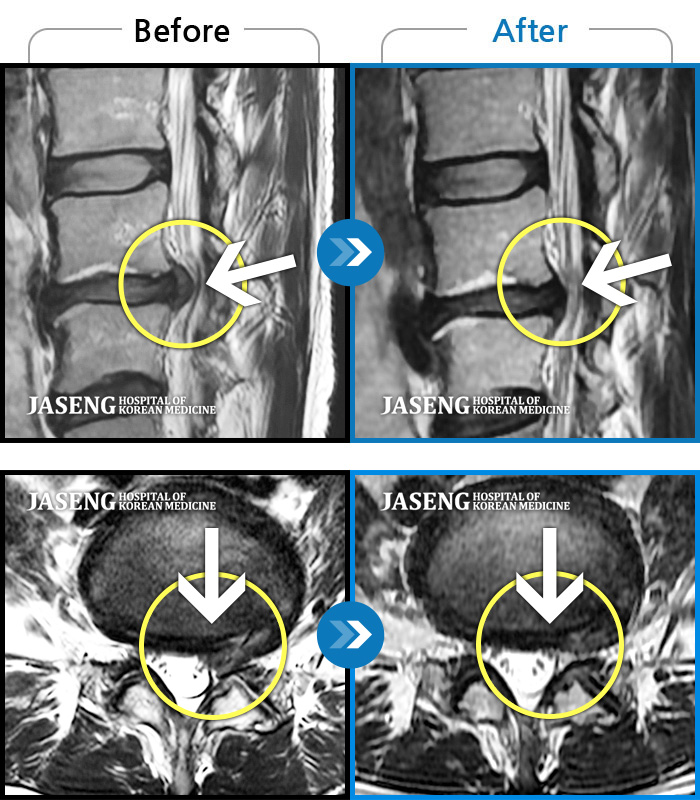

24년 3월 디스크파열 진단받고 극심한 통증으로 입원하여 김재영원장님께 치료받은 후 증상이 매우 호전되어 퇴원한 경험이 있습니다. 원장님께서 퇴원무렵 컨디션 관리를 엄청 당부하셨지만 근무하는 과정에서 발생하는 어쩔수 없는 과로와 극심한 스트레스는 서서이 좋아지던 저의 디스크 통증을 급기야 재발하게 만들었습니다. 7월말 다시 시작된 왼쪽 종아리와 발가락으로 퍼지는 심한 통증과 몸살로 더이상 근무를 계속할수 없어서 급하게 원장님을 뵙고 입원 치료하게 되었습니다. 김재영 원장님께 진료받고 극심했던 방사통이 진통제 없이 생활하기 까지 호전된 경험이 있고 원장님께서도 저의 상황을 어느정도 아시고 계셔서 이번에는 처음 디스크 터졌을때처럼 엄청 겁먹지 않고 원장님께 사소한 증상 하나하나 말씀드리면서 차분하게 치료받을 수 있었습니다. 제가 직장다니면서 힘든 마음으로 다시 입원하게 된 상황을 이해해 주시고 치료가 빠르게 될수 있도록 매일 소소한 증상 하나하나 신경쓰셔서 치료해주시고자 애써 주셔서 진심으로 감사했습니다. 심한 몸살이 디스크 통증과 함께 와서 소화도 안되고 기운도 없이 입원 첫주 무척 힘든 시간을 보냈습니다. 원장님께서는 소화가 잘 되게 침치료도 병행해 주시고, 소화제 종류도 다양하게 바꿔가며 저의 컨디션이 되돌아 올수 있게 처방을 해 주셨습니다. 무수히 많은 환자를 진료하시는 바쁘신 진료시간 중에서도 저의 증상을 매일 편하게 말씀 드릴수 있게 대해 주셔서 소소한 증상까지 말씀 드려 본의 아니게 원장님을 피곤하게 해드렸습니다. 입원 9일차 정도되니 그렇게 아팠던 종아리 통증은 거의 사라지고 소화기능도 조금씩 회복되고 있습니다. 통원치료때도, 입원치료때도 늘 한결같이 저의 증상을 귀담아 들어주시고 치료가 빠르게 될수 있도록 애써 주셔서 고맙습니다. 침 치료시에 어쩔수 없이 듣게 되는 다른 환자분들과 원장님과의 대화속에서도 치료받으시는 어버님 아버님들께서 원장님께 아픈 곳을 편히 말씀하시는것이 느껴졌습니다. 원장님께서도 일일이 다 성의껏 어르신들 말씀 귀담아 들어주시고 치료해 주시는것을 보니 원장님께서는 참으로 인품마저 다정하신 분 같았습니다. 거기에 아픈 통증도 꼭꼭 잡아주시니 원장님께 진료받는 많은 환자들이 원장님의 마음에 심적으로 안정을 받으시고 원장님의 전문적인 의료 도움을 크게 받는것 같습니다. 원장님께서 환자를 대해 주시는 따뜻함, 실력있는 의술 덕분에 제가 입원하는 기간 마음 편하게 치료 받을수 있었습니다. 통증이 자주 재발하면 완치되기가 힘드니 조심해야 된다는 원장님 조언 잘 새겨듣고 올 하반기에는 다시 입원하지 않도록 노력해 보겠습니다. ^^ 원장님께서도 남은 여름 건강 잘 챙기세요~~~ 고맙습니다. 김재영 원장님 ^^

저는 허리디스크 파열로 3월 1일부터 입원하여 3주째 해운대 자생 김재영 원장님께 입원진료를 받고 있습니다.

이번주에 퇴원할 예정이라 그동안 원장님께 진료 받고 조금씩 나이지고 있는 부분에 대해 진심으로 감사한 마음을 전하고 싶습니다.

허리 디스크 파열이라는 사실을 모르고 단순하게 허리디스크가 조금 튀어나왔을거라고 생각하고 이전 교통사고로 생긴 두통 치료를 김재영 원장님께 진료받고 나은 기억이 있어 혹시나 하여 원장님과 상담을 했습니다.

김재영 원장님께서 혹시 모르니 그래도 MRI를 찍어보고 정확히 원인을 알고 치료를 하자고 권유하셔서 MRI를 찍게 되었습니다. 결과는 디스크 파열로 심각한 상황이었습니다.

결과를 보시고 원장님은 한방 치료에 대한 막연한 희망을 주시기 보다는 정확한 저의 상황에 대해 설명해 주셨고 제가 어떤 방향을 원하는지 귀담아 주셨습니다.

저는 수술이 당장 시급한, risk가 상당히 있는 MRI 결과였지만 갑작스러운 결과에 수술을 바로 하기엔 너무 겁이 나서 일단 입원하여 원장님 치료를 받아보기로 마음먹고 바로 입원했습니다.

지옥같은 1주일이 지나고 아주 조금씩 방사통이 약해지기 시작했고 지금 입원 3주차에 접어들어서는 그렇게 심했던 방사통은 낮에 근무가 가능할 정도로 호전되었습니다.